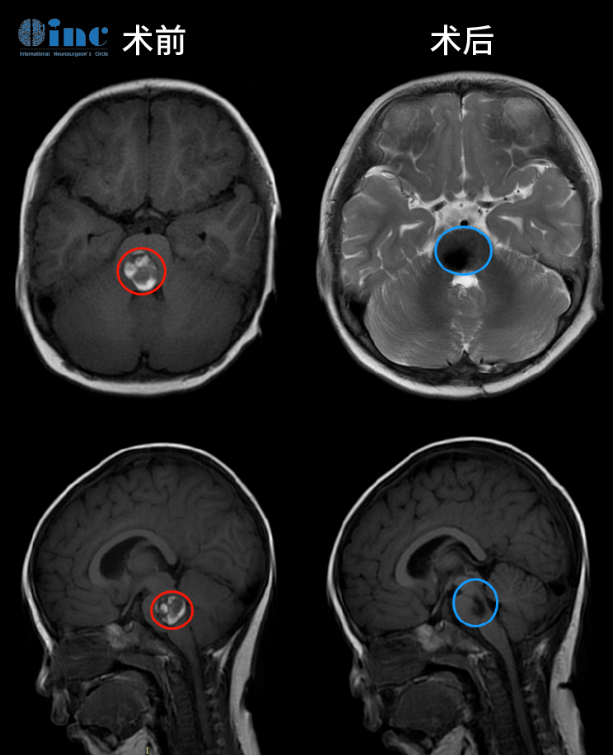

治疗过程:在苏州大学附属儿童医院,巴教授与国内手术医生围绕病情展开了充分的讨论和评估,并根据患者病变的特点较终确定了相对创伤小的手术入路和手术方案。手术由巴特朗菲教授亲自操刀,将2cm大小的脑干桥脑海绵状血管瘤完全剥离。

伊伊术前术后MR影响对比全切病灶

术后一个半月复查,原有的斜视、走路不稳症状都消失了,面瘫减轻,行动能力完全正常,没出现任何新的并发症。现在,伊伊已经回归了原有的活力,而且今后不会再被这个疾病所折磨了,这是让伊伊父母无比欣慰和感恩的。